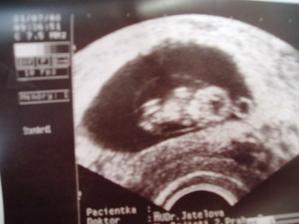

19.8. - NT screening: Apolinář, krásný zážitek i pro tatínka, mimčo se vrtělo, musela jsem zakašlat, aby se správně natočilo. Vše je v nejlepším pořádku, nt 1,8, jsme zdraví, 2.foto, na kterém se mimčo hoooodně podobá mamince - její lícní kosti, nosánek i nadočnicové oblouky 🙂